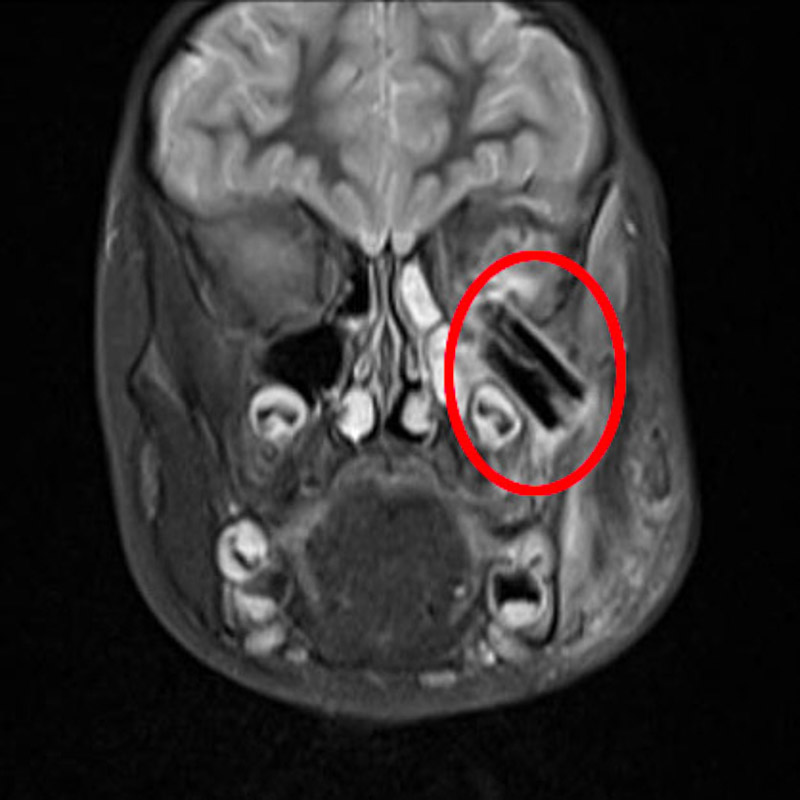

接诊医生得知患儿曾摔跤受伤,便推断伤口可能有异物残留,立即安排其入院进行详细检查。检查发现树枝从面部直插颞下窝至眼球后方,还有零星碎片断在颅底,导致眼球位移,面颊部、鼻部、眼部感染,情况不容乐观。

术者顺着树枝刺入的方向,小心翼翼分离周边组织,将多片长达3厘米的树枝残留物取了出来,经过两个多小时,顺利将伤口内异物全部清除并缝合还原。术后患者平安返回病房,医护人员给予患者抗炎、消肿、补液、换药等对症支持治疗,目前,患儿已成功出院。